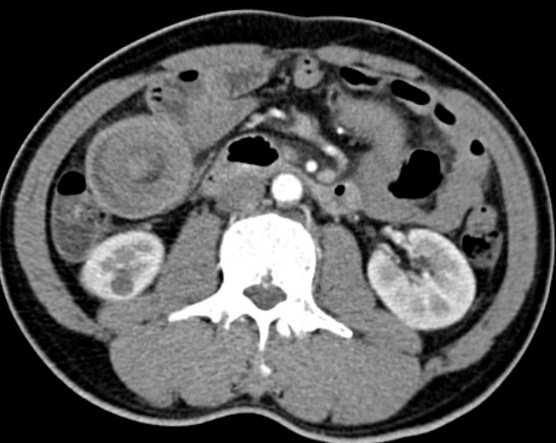

Khám lâm sàng thấy:  Đau bụng vừng thương vị, bụng mềm, phản ứng thành bụng (-), mass mơ hồ vùng thương vị. Chụp Xquang bụng không chuẩn bị tư thế đứng (Không thấy liềm hơi dưới cơ hoành 02 bên, không thấy hình ảnh mức hơi dịch điển hình). Kết quả siêu âm bụng: Vùng thượng vị có hình ảnh búi lồng kích thước # 5,1x7,1x10,3 cm. Bệnh nhân được chỉ định chụp CT scanner ổ bụng kết quả: Hình ảnh lồng ruột non vùng thượng vị dài trên 30cm với hình ảnh bia bắn và bánh mỳ kẹp thịt(Hình 1 và 2).Xét nghiệm công thức máu có: Bạch cầu 6,8 G/L, neurophile 74%. Thiếu máu với Hb: 84g/l, Hct: 28%, MCV: 67,74 fl, 20,16 pg, Tiểu cầu: 291G/l.

Hình 2. Hình ảnh bánh mỳ kẹp thịt